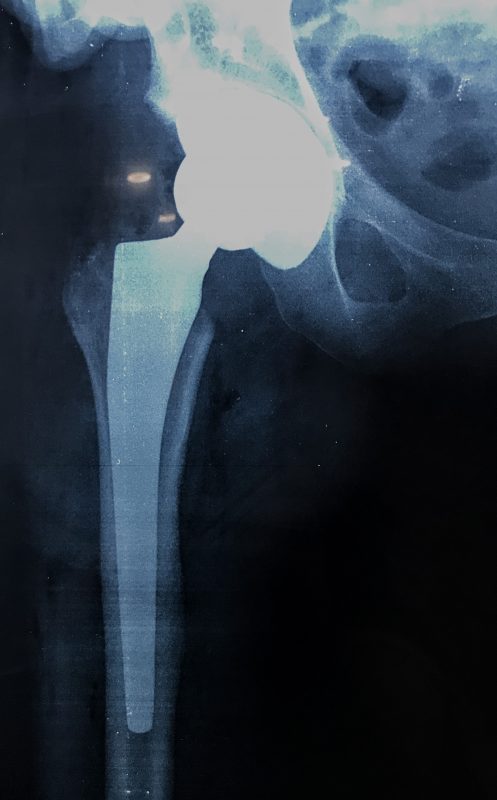

Παραδοσιακά οι αρθροπλαστικές ισχίου αποτελούνται από μια μεταλλική μπάλα – σφαίρα τοποθετημένη σε μια πλαστική κοιλότητα (κοτυλιαία πρόθεση).

Η πλαστική επιφάνεια στήριξης φθείρεται με την πάροδο του χρόνο, με ρυθμό μάλλον σχετιζόμενο με το επίπεδο δραστηριότητας του ατόμου. Αυτό έχει σαν επακόλουθο νεότεροι ασθενείς με μεγαλύτερο προσδόκιμο ζωής να έχουν αυξημένο ρίσκο αναγκαιότητας δεύτερης αρθροπλαστικής ισχίου (αναθεώρησης – Revision) επέμβαση που είναι πολυπλοκότερη και υπόκεινται σε υψηλότερο κίνδυνο επιπλοκών. Βάση των ανωτέρω, ιστορικά, η αρθροπλαστική ισχίου σπανίως εφαρμοζόταν σε ασθενείς κάτω των 60 ετών.

Χάρη στα νέα τεχνολογικά επιτεύγματα έχουν παραχθεί επιφάνειες στήριξης που ανταποκρίνονται σε μεγαλύτερα επίπεδα δραστηριότητας και αναμένεται να έχουν μεγαλύτερη διάρκεια ζωής. Αυτές οι καινούριες επιφάνειες στήριξης είναι συνήθως μέταλλο πάνω σε ειδικό σκληρότερο πλαστικό ή κεραμικό πάνω σε κεραμικό. Ως εκ τούτου, είναι τώρα πολύ πιο σύνηθες, νεότεροι ασθενείς να χειρουργούνται καθώς η πλειονότητα αυτών, που η αρθρίτιδα τους προκαλεί αφόρητους πόνους, επιλέγουν να έχουν ποιότητα ζωής από το να ζουν με τον πόνο.